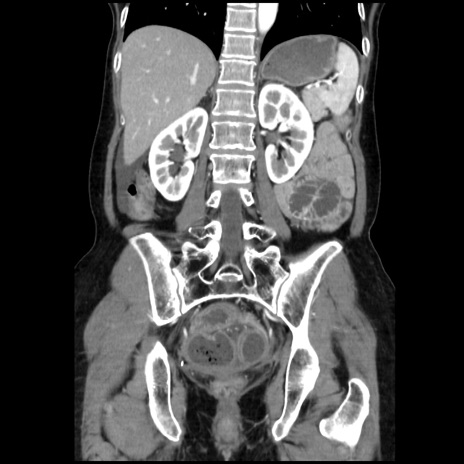

症例32(冠状断像)

【症例】40歳代 女性

【主訴】上腹部痛、嘔気・嘔吐

【現病歴】約9時間前頃から急に上腹部痛、嘔気、嘔吐が出現。改善しないため救急要請。

【既往歴】子宮頚癌(広汎子宮全摘術、放射線療法)、腸閉塞

【身体所見】腹部:平坦、軟、腸雑音亢進、上腹部を中心に腹部全体に圧痛あり。

【データ】WBC 8400、CRP 0.03